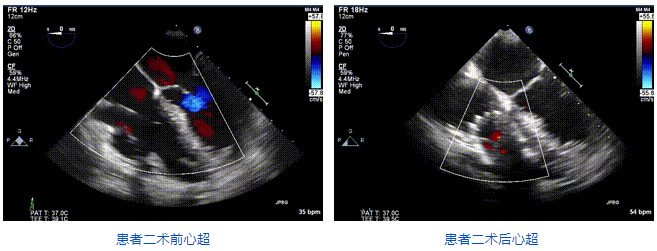

2021年12月24日,復(fù)旦大學(xué)附屬中山醫(yī)院葛均波院士團(tuán)隊(duì)成功應(yīng)用LuX-Valve Plus為一例極重度三尖瓣反流(TR)合并房顫、房缺的患者完成了經(jīng)血管三尖瓣置換術(shù),這是在前基礎(chǔ)上,本周完成的第三例經(jīng)血管三尖瓣置換手術(shù),葛均波院士、周達(dá)新教授等與心外科魏來教授、賴顥教授,心超室的潘翠珍教授、李偉教授及麻醉科的郭克芳教授共同完成了本周手術(shù),均獲得圓滿成功!患者術(shù)后超聲顯示無TR,臨床癥狀明顯改善。本周手術(shù)的成功也為L(zhǎng)uX-Valve Plus救治性臨床研究添上了濃墨重彩的一筆。

三例患者入院后,葛均波院士團(tuán)隊(duì)周達(dá)新教授、潘文志教授、張?jiān)床┦俊㈥惿┦考靶某业呐舜湔浣淌凇⒗顐ソ淌趯?duì)患者的情況進(jìn)行詳細(xì)評(píng)估和討論,最終決定為三例患者選擇LuX-Valve Plus40mm、50mm和50mm型號(hào)的瓣膜進(jìn)行手術(shù)治療。手術(shù)后即刻拔除氣管插管,術(shù)后患者三尖瓣反流癥狀得到顯著改善,復(fù)查心超結(jié)果顯示人工三尖瓣瓣膜支架固定穩(wěn)定,瓣葉關(guān)閉形態(tài)未見異常,未見明顯反流。